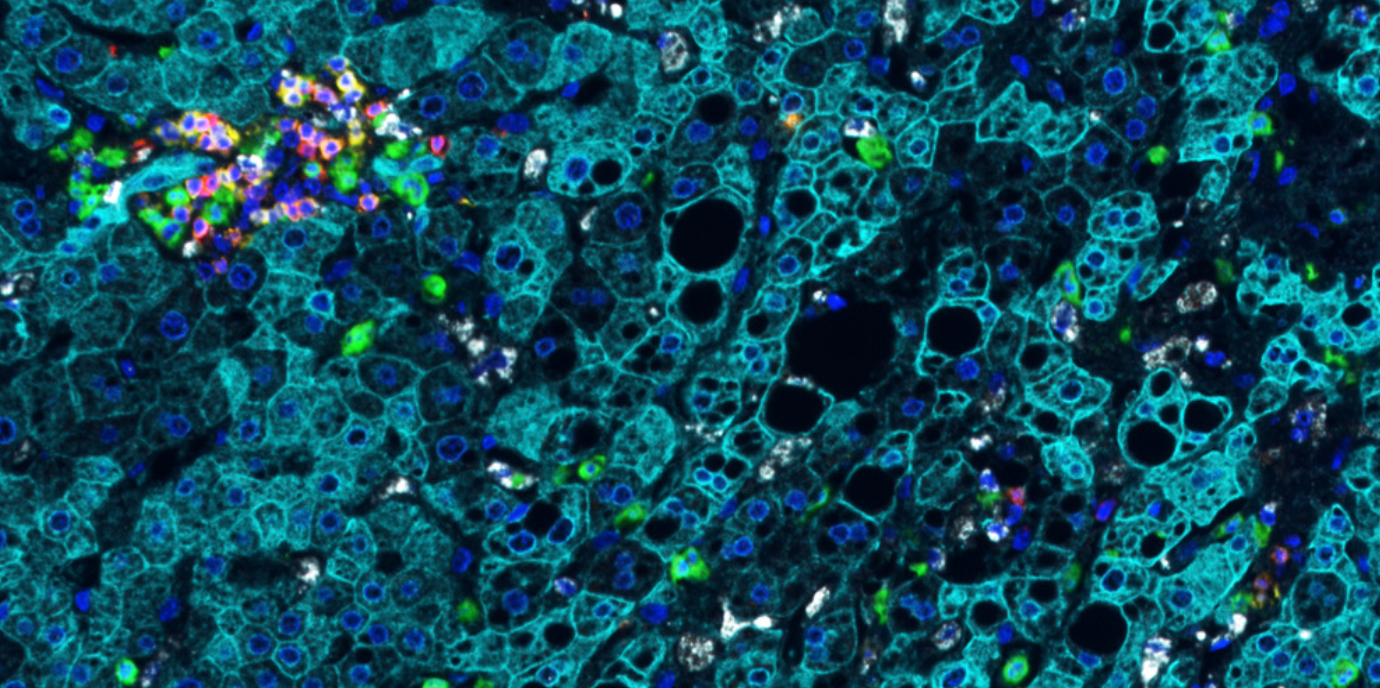

Basierend auf der intensiven Zusammenarbeit und der Bündelung innovativer methodischer Kompetenzen aus den Teams um Stefan Schneeberger und Dominik Wolf, Direktor der Univ.-Klinik für Innere Medizin V (Hämatologie und Onkologie), gelang es nun, wichtige Einblicke in die Dynamik von Immunzellen der Leber vor und während der Maschinenperfusion zu gewinnen. Mittels Einzelzell-RNA-Sequenzierung und anderen Validierungsmethoden von Lebern vor und unter normothermer Maschinenperfusion erstellten die Innsbrucker Forscher:innen, darunter die Erstautor:innen Theresa Hautz, Margot Fodor und Stefan Salcher, eine Immunkartographie der Leber. Das angesehene Fachjournal Nature Communications berichtet darüber.

„Wir waren überrascht, wie rasch und wie viele Entzündungszellen aktiviert werden und wie schnell sie sich fortbewegen“, berichtet Transplantationsexperte Schneeberger. Noch nie zuvor wurde beobachtet, dass die in der Leber beheimateten Leukozyten innerhalb einer Stunde mobilisierbar sind und auf dem Weg in den künstlichen Maschinen-Blutkreislauf auch ihren Aktivierungsstatus – von pro-inflammatorisch bis regenerativ – verändern. Mit der an der Innsbrucker Univ.-Klinik für Hämatologie und Onkologie von Stefan Salcher etablierten Einzelzellanalyse konnten zudem bislang nicht kartierte Neutrophile Granulozyten (spezifische Immunzellen) in menschlichen Spenderlebern gezeigt werden. Diese Zellen sind unter anderem für den Gewebeschaden und für eine mögliche Abstoßung nach der Transplantation von zentraler Bedeutung.